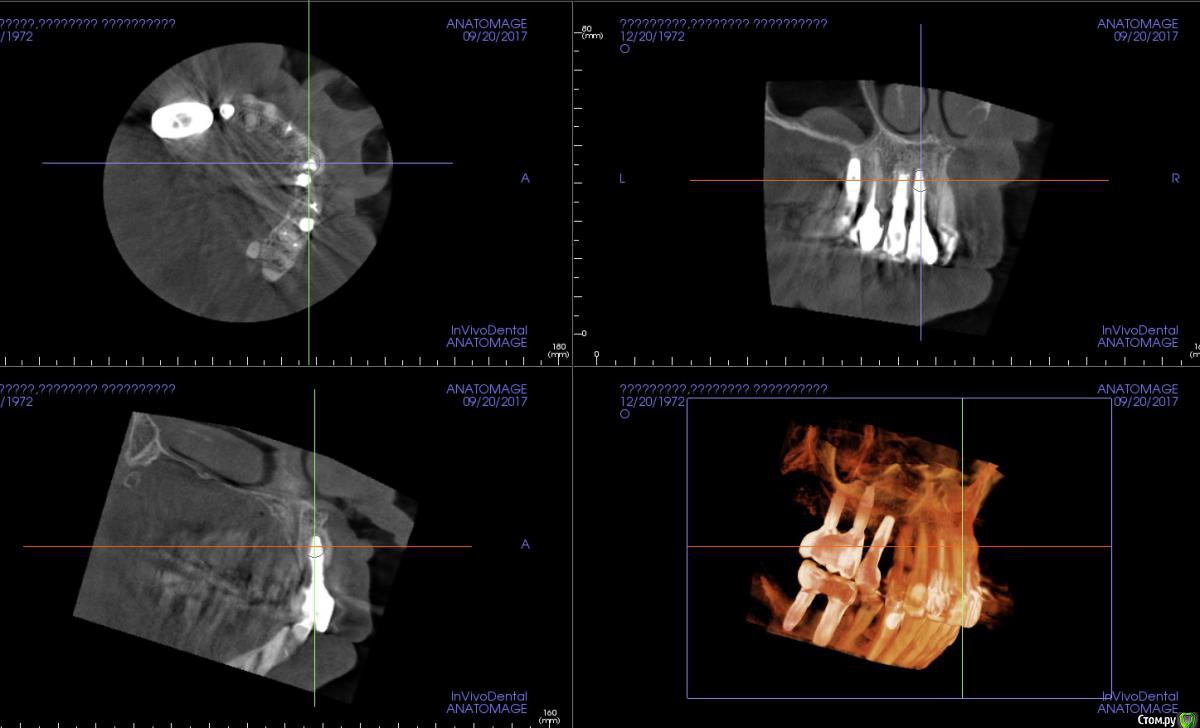

Irouil Опубликовано 11 августа, 2018 Поделиться Опубликовано 11 августа, 2018 Работа не моя В 2015 установленный 2.2, в 2016 - 2.1. зондируется около 5 мм вестибулярно от 2.1, около 7 между ними, около 3-4 у 2.2. оголился абатмент 2.2. Насколько адекватно будет тащить это на мягких тканях? Хочу с бугра в сосок и вестибулярно с неба. Ссылка на комментарий

колесников Опубликовано 11 августа, 2018 Поделиться Опубликовано 11 августа, 2018 Я бы если и взялся с десной работать,то только с заменой абатмент на 22ом. Мягким тканям нужна поддержка,с такого абатмент все улетит снова. Если нет возможности изменить форму абатмента,какой нибудь из имплантолов заглушил и предложил консоль. Правда на такой вариант, ни один из имплантов не внушают доверия. 1 Ссылка на комментарий

колесников Опубликовано 13 августа, 2018 Поделиться Опубликовано 13 августа, 2018 Когда кости нет ,вы проводите деснев аугментацию ,о которой сейчас речь,зачем? Очевидно чтобы компенсировать дефицит объема и создать каркас для маргинальной слизистой. Мягкие ткани не растут вертикально,Лоскуту самому нужна поддержка ,чтобы сохранять первоначальную форму. Этой поддержкой может быть корень зуба или костные пики, ни того ни другого в данном случае нет. За что будет держаться лоскут,как питаться,как форму сохранять? Очевидно что он осядет. Дайте ему дополнительные «зацепы» в гладких и вертикальных стенках абатмента. Ссылка на комментарий